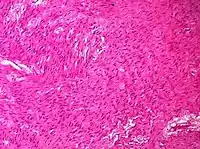

| Adult granulosa cell tumor | 1% | Almost 100% | Small, bland, cuboidal to polygonal cells in various patterns.[9] | ![]() | |